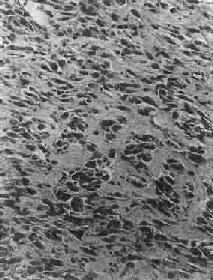

图17-3 骨软骨瘤 图示特征性的三层结构,即最表浅的纤维层,中间的软骨层(软骨帽)和深部的松质骨 【临床病理联系】 骨软骨瘤一般无明显症状,只是局部肿块形成。有时肿块压迫周围组织,引起疼痛和不适。如果肿块体积迅速增大,软骨帽增厚至1cm以上,则须考虑恶变的可能,这在多发性者比单发性者多见。本瘤如手术切除不彻底,则易复发,多发生在1年或数年后。 (二)软骨肉瘤 软骨肉瘤(chondrosarcoma)是从软骨细胞发生的原发性恶性骨肿瘤,由肿瘤性软骨细胞及软骨基质组成。软骨肉瘤是颇为常见的恶性骨肿瘤,其发病率仅次于骨肉瘤,其发病年龄多在中年以后,多见于40~70岁,根据发病部位不同,可分为中央型及周围型两种。中央型从骨髓腔发生,肿瘤为骨皮质所包绕或穿破骨皮质,多见于长管状骨,特别是股骨和胫骨;周围型从骨肿瘤表层出发,向周围软组织及骨皮质侵犯,多见于骨盆、肩胛骨及肋骨等。少数软骨肉瘤来自软骨瘤和骨软骨瘤之恶变。 【病理变化】 肉眼观,中央型软骨肉瘤主要发生在骨髓腔内,呈灰白色、半透明的分叶状肿物,其中常见淡黄色的钙化或骨化小灶。这些钙化或骨化小灶在X线片上可以看到,对诊断软骨肉瘤很有帮助,但高度恶性的软骨肉瘤钙化常不明显。随肿瘤的增大可使骨髓腔变大并侵犯骨皮质,骨外膜受刺激后,可有反应性新骨形成,使受累骨皮质增厚。恶性程度较高的软骨肉瘤,在早期即可穿破骨皮质,向软组织内扩展,形成较大的肿块,周围没有新骨形成。外围型软骨肉瘤瘤体主要在骨外,其表面被覆一层薄而不完整的包膜。以上两型软骨肉瘤均常发生粘液变、出血及囊性变等继发性变化。 镜下观,肿瘤的分化程度差异很大,分化好的软骨肉瘤在镜下易误诊为软骨瘤,但在肿瘤的边缘可以找到瘤细胞的异型性,如核肥大、深染,出现较多的双核、巨核和多核瘤巨细胞,并可见明显核仁(图17-4)。在分化差的软骨肉瘤则上述瘤细胞的异型性很明显,核分裂像也多见。软骨肉瘤的基质可为与一般透明软骨相似的透明基质,也可为粘液样基质,常见于恶性程度高的软骨肉瘤。

图17-4 软骨肉瘤 软骨细胞大小不等,有的较大。许多细胞有肥硕的胞核,有的有双核 【临床病理联系】 局部疼痛及肿块往往是软骨肉瘤的主要症状。近关节的肿瘤常影响关节活动。盆骨的巨大软骨肉瘤可压迫邻近器官,引起相应症状。软骨肉瘤的分化程度对临床经过有一定影响,分化较好的软骨肉瘤往往生长较慢,预后较好。软骨肉瘤一般比骨肉瘤生长慢,转移也较晚。血道转移可至肺、肝、肾及脑等处,淋巴结转移极罕见。软骨肉瘤术后常易复发,多次复发常使恶性程度增加。 (三)骨巨细胞瘤 骨巨细胞瘤(giant cell tumor of bone)是一种具有局部侵袭性及复发倾向的原发性骨肿瘤。由梭形和卵圆形的基质细胞(stromal cell)及大量散布在其间的多核巨细胞组成,肿瘤间质富于血管。由于本瘤内有大量多核巨细胞,因而称为巨细胞瘤;又因过去认为这些多核巨细胞是破骨细胞,故也称为破骨细胞瘤(osteoclastoma)。本瘤的组织来源未明,以上各名称纯系形态学的描述性命名。在我国骨巨细胞瘤的发病率较高,仅次于骨软骨瘤和骨肉瘤,居第三位。本瘤好发年龄为20~40岁的青壮年,性别无明显差异。 【病理变化】 骨巨细胞瘤多发生于四肢长骨的骨骺端,尤以股骨下端及胫骨上端为多见,约占半数左右,其次为桡骨下端、尺骨下端或肱骨上端等部位。长骨以外则以脊椎为多见。 肉眼观,本瘤常侵犯骨骺线已闭合的长骨端,大多数位于骨骺,早期常为偏心性生长,增大的肿瘤使骨皮质受累而向外膨胀。在肿瘤周围往往有菲薄的骨壳,乃由骨内、外膜反应性新生骨构成,肿瘤的境界比较清楚。肿瘤内原有松质骨大部分或全部消失,瘤内常有纤维组织或骨性间隔。由于肿瘤组织的溶骨性破坏,常造成病理性骨折(图17-5)。肿瘤组织呈灰红色,质软而脆,较大的肿瘤常合并出血及坏死,并伴有囊性变而形成大小不等的空腔,囊腔内含有浆液性或血性液体。晚期病例骨性包壳如果被破坏,则可侵犯软组织形成肿块。关节软骨有抗肿瘤浸润的作用,关节软骨下骨间质可完全被破坏,致使关节软骨失去支持而扭曲变形。